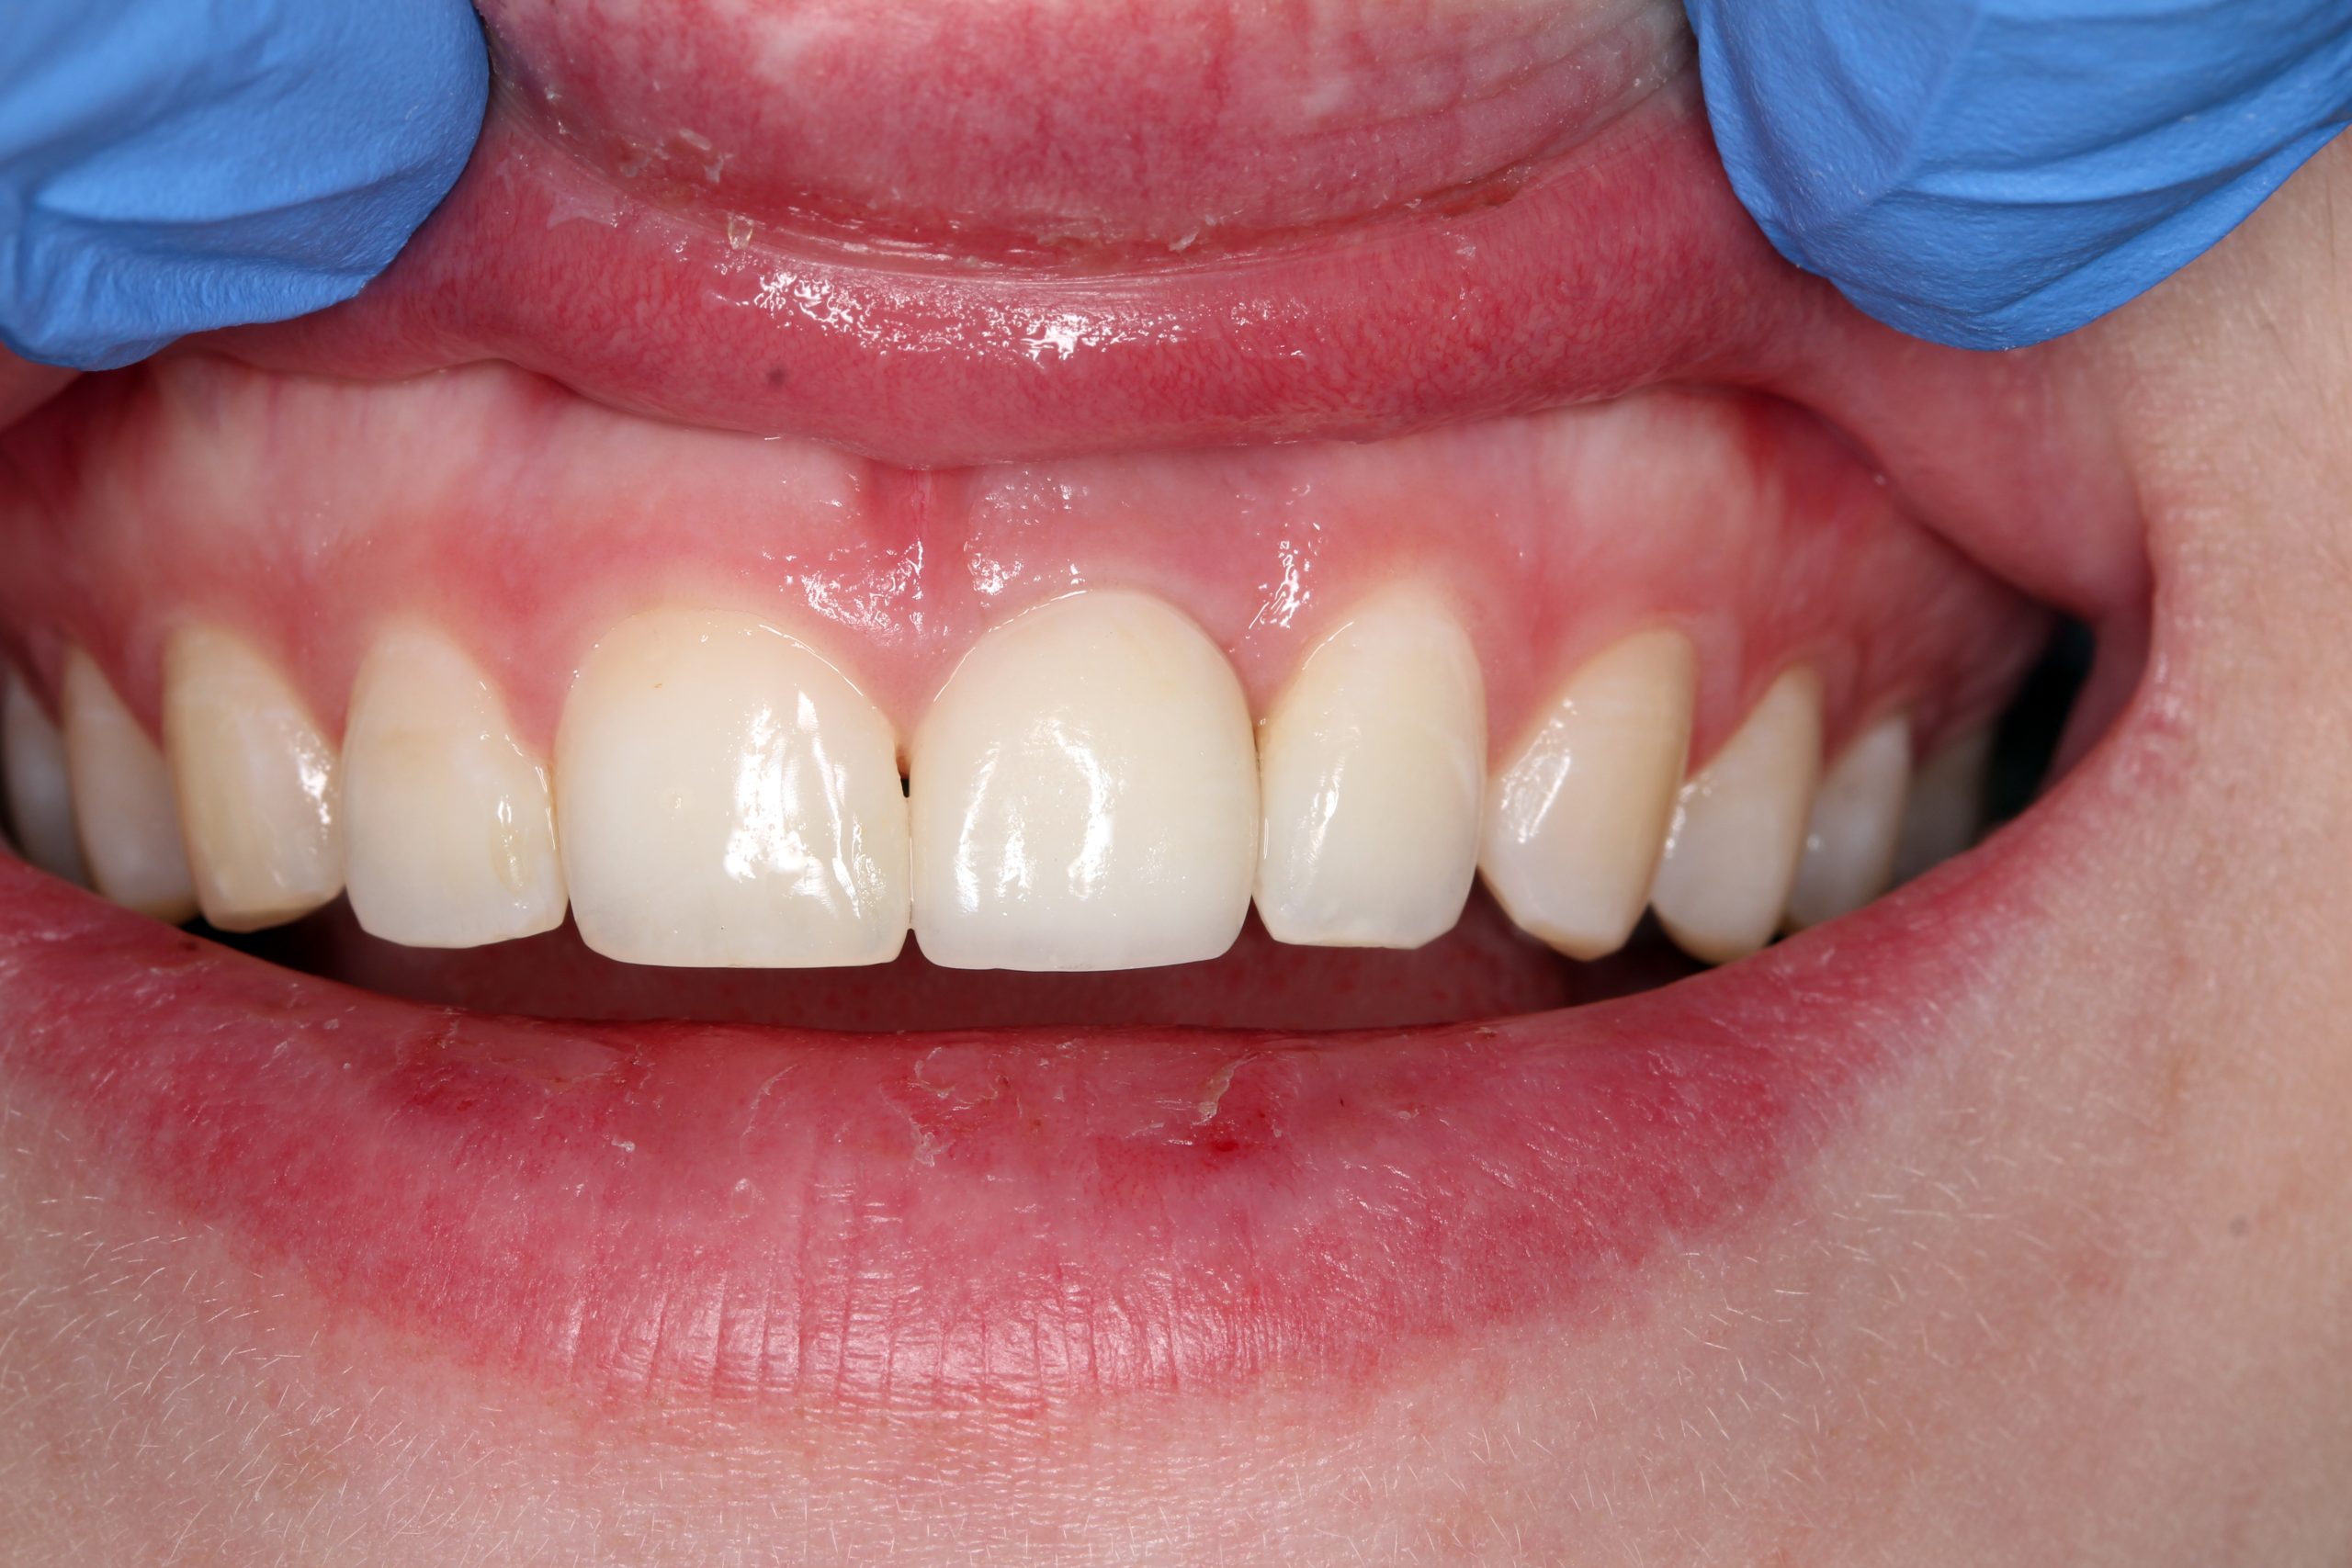

Das Lächeln der Patientin beim Recall nach drei Jahren. Durch minimalinvasive chirurgische Eingriffe und die Schonung des umliegenden Gewebes konnte ein bestmögliches ästhetisches und gleichwohl funktionelles Ergebnis erzielt werden.

Das Röntgenbild nach drei Jahren zeigt ebenfalls eine verheilte Alveole ohne resorptive Veränderungen.